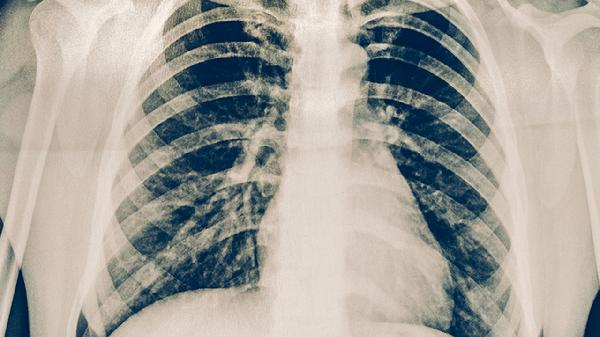

耐药性肺结核经过规范治疗通常可以彻底根治,但治疗周期较长且需严格遵循医嘱。耐药性肺结核主要由结核分枝杆菌对一线抗结核药物产生耐药性引起,临床表现为长期咳嗽、低热、咯血等症状,需通过痰培养和药敏试验确诊。

耐药性肺结核患者需坚持完成整个疗程,即使症状消失也不可中断用药。治疗期间每月复查肝肾功能,每3个月进行胸部CT评估。痊愈后仍要定期随访2年,保持充足睡眠和适度运动,避免过度劳累诱发复发。出现持续咳嗽、体重下降等症状需及时复诊。